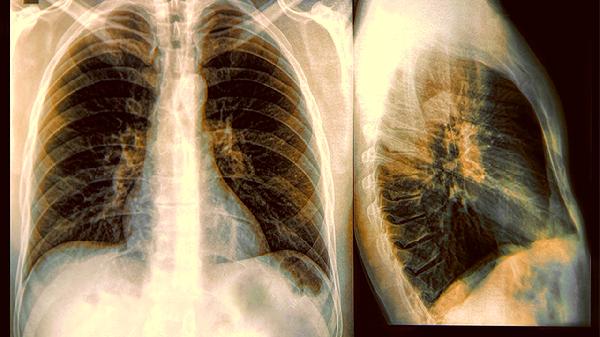

肺气肿是肺泡壁被破坏形成的永久性扩张,就像过度拉伸的橡皮筋失去回弹力。当同时出现气道阻塞和持续气流受限时,就会升级为慢阻肺这个"终极大BOSS"。

单纯肺气肿患者可能只是运动后气短,但慢阻肺患者连刷牙都可能喘不上气。肺功能检查中FEV1/FVC比值小于70%就是慢阻肺的"身份证"。

每吸一支烟相当于往肺泡里扔微型炸.弹,老烟民肺部CT上的黑色空洞就是证据。电子烟产生的气溶胶同样会刺激呼吸道。